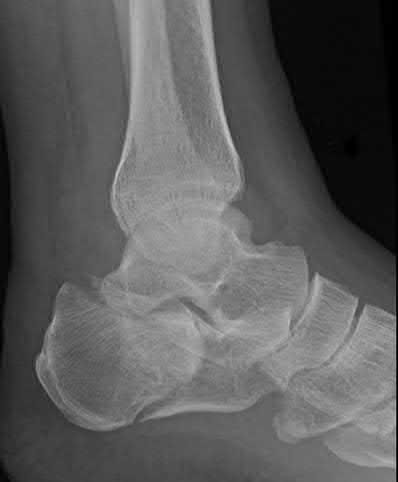

A 25-year-old male sustains an ankle fracture dislocation and undergoes open reduction and internal fixation. He returns to clinic five months following surgery complaining of continued ankle pain and instability with weight bearing. His immediate post-operative AP radiograph is seen in Figure A. Which of the following could have prevented this patient from developing persistent pain?

The patient presents with continued ankle pain and instability following open reduction and internal fixation. The radiograph in figure A demonstrates inadequate restoration of fibular length, likely leading to continued tibiotalar instability.

Illustration A demonstrates fibular malreduction with dislocation of the fibula anterior to the tibial incisura. Illustration B shows a comminuted fibula fracture along with a measurement of length from an intact fibula. The arc from the lateral process of the talus to the peroneal groove of the distal fibula is known as the "dime" sign and should remain unbroken if fibular length has been restored. Illustration C demonstrates the use of a push-pull screw and lamina spreader to regain length intraoperatively for a comminuted fibula fracture.

Chu and Weiner review management of malunions of the distal fibula. The authors state that restoration of fibular length, alignment and rotation leads to reduction of the talus, provides a buttress to talar motion in the setting of an incompetent deltoid, and allows the syndesmotic ligaments to heal at the appropriate tension.